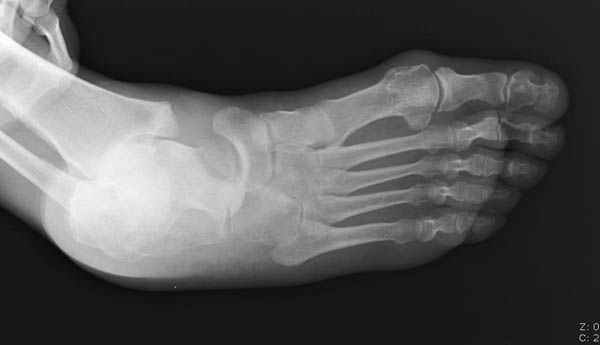

Вдогонку по поводу перелома таранной кости, больная 81, не страдает диабетом, перелом закрытый, в первый же день поступления ограничились временным наружным фиксатором (как на снимке).

За пару недель насчитал 5 больных с переломом таранной кости, из них двое с двусторонним повреждением.

Примеры на снимке...